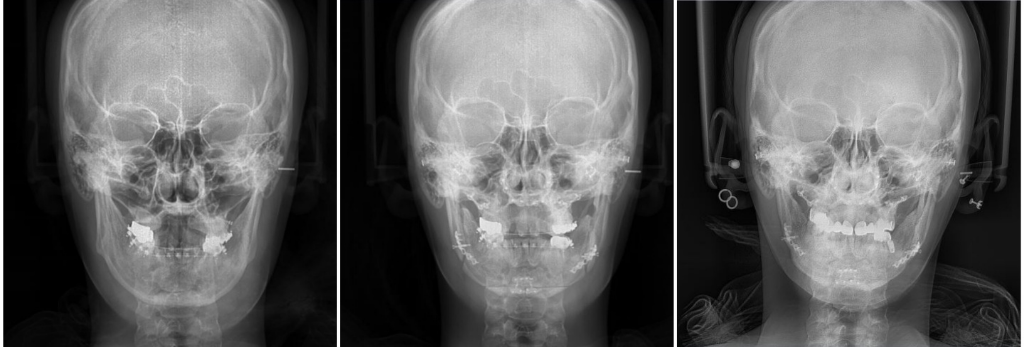

양악 재수술 케이스 일까요? 선생님 부탁드려요

양악수술 전 후 확인 부탁드려요ㅠㅠ너무 답답해서요

10년전 미용목적이였구요, 딱히 문제가 있는건 아니였어요.

제 욕심에.. 그때는 인터넷과 정보가 부족하여 교정을 빨리 끝내고 싶다는 욕심과 그때 당시 tv프로그램에 홀려 성형외과에 그냥 가서 해달라고 했어요. (또 교정을 하는지 모르고 교정을 하는지 모르고 병원에서도 설명을 안해주었어요ㅠㅠ /원래도 부정교합아니였는데 살짝 돌출끼에 하였어요)

수술 후 제 뼈가 이상한것 같은데 제눈이 이상한건가여?

얼굴형부터 중심선까지 너무 틀어져서요

한쪽이 치아도 그렇고 뒤로 빠져있어요,

(10년 지났어요/사진은 수술전/수술 바로 직후예요)

• 1번 째 사진

• 2번 째 사진

• 3번 째 사진